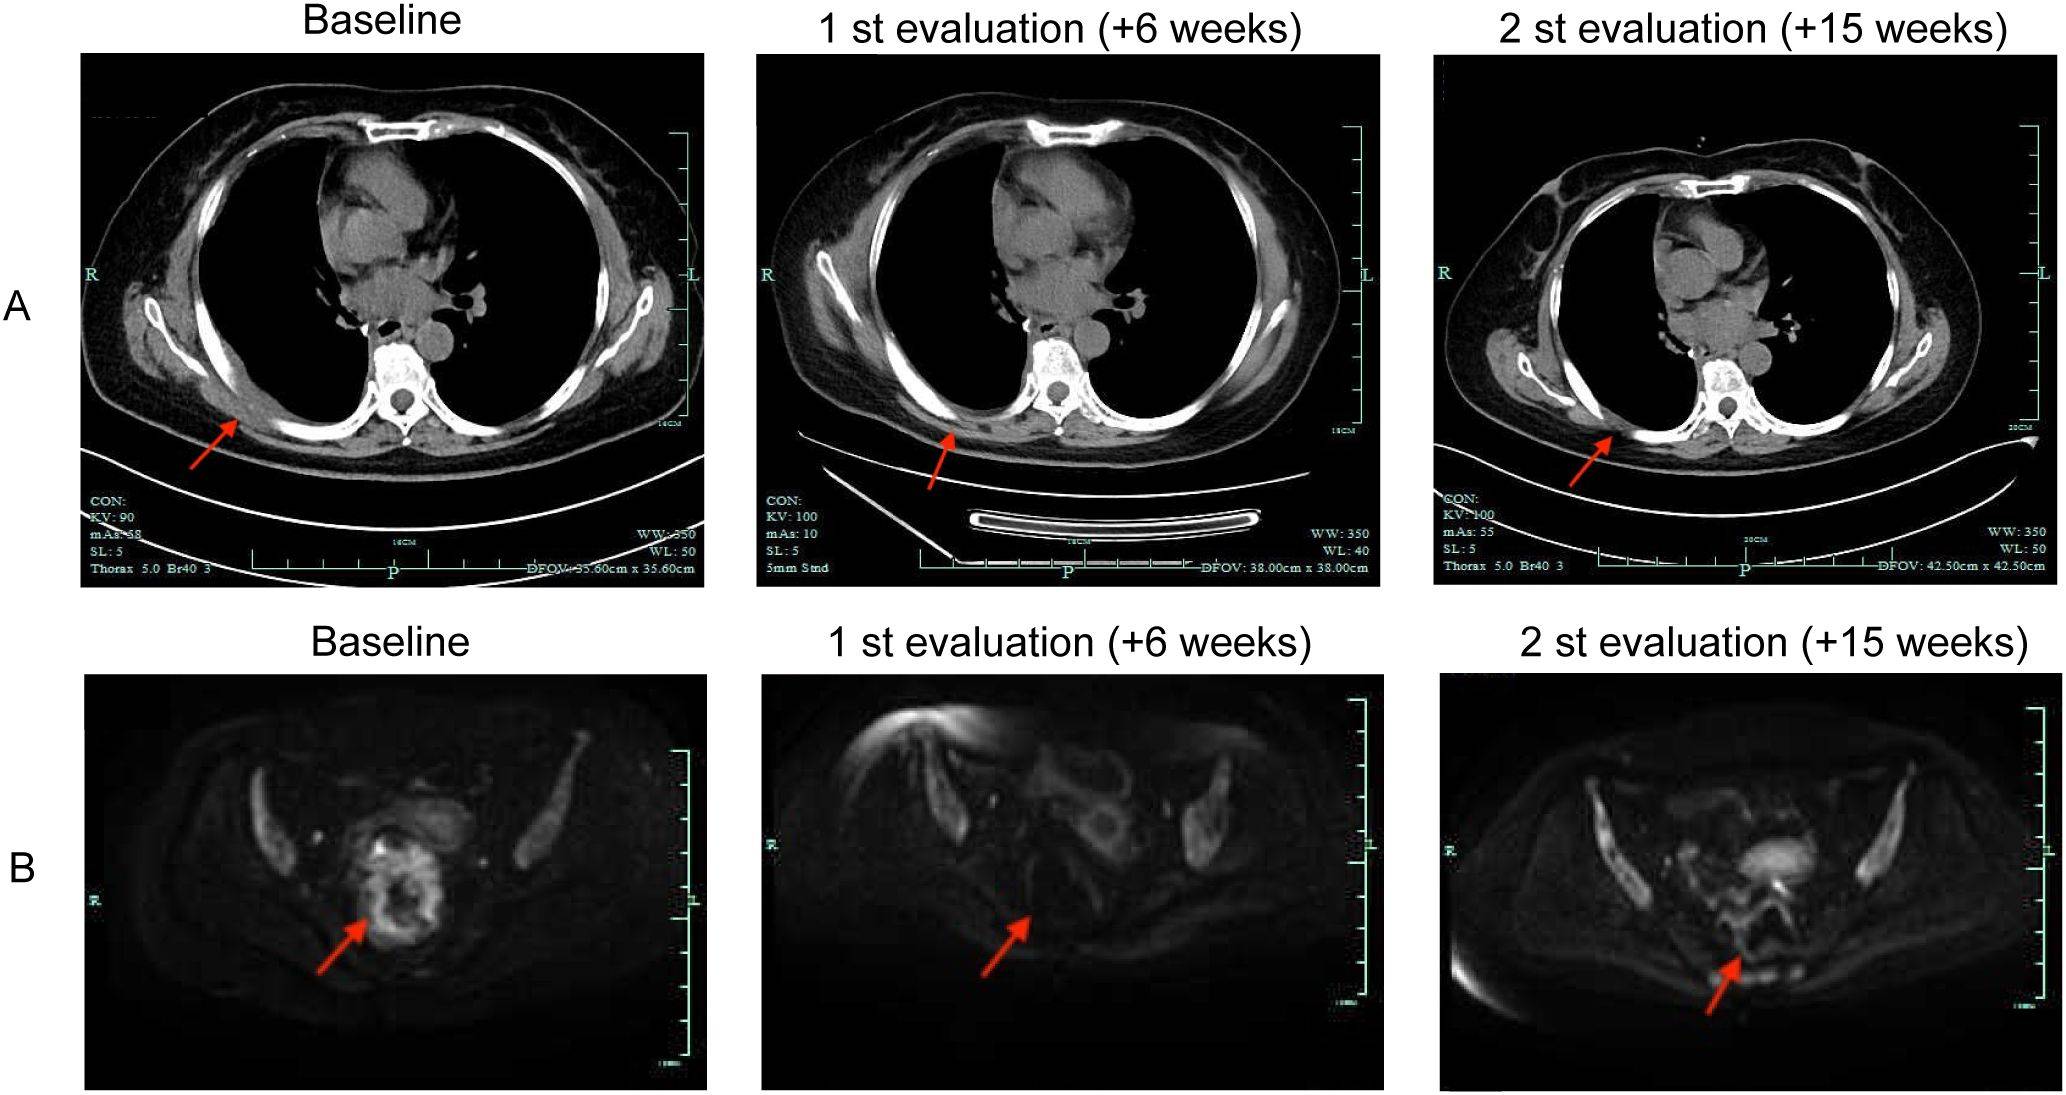

患者于2025年4月8日开始接受艾托组合抗体(Q1706)(每3周一次)的免疫治疗。两个周期后的胸部CT显示右侧胸膜增厚明显改善,盆腔MRI显示肠壁受累减少(图3)。治疗5个周期后,病灶进一步缩小,且未观察到免疫相关不良反应。肿瘤标志物CEA和CA125保持在正常范围内。患者持续对免疫治疗产生反应 。

图 3.艾托组合抗体治疗前后的放射影像。(A)代表性的胸部计算机断层扫描 (CT) 图像。(B)代表性的盆腔增强磁共振成像 (MRI) 图像。